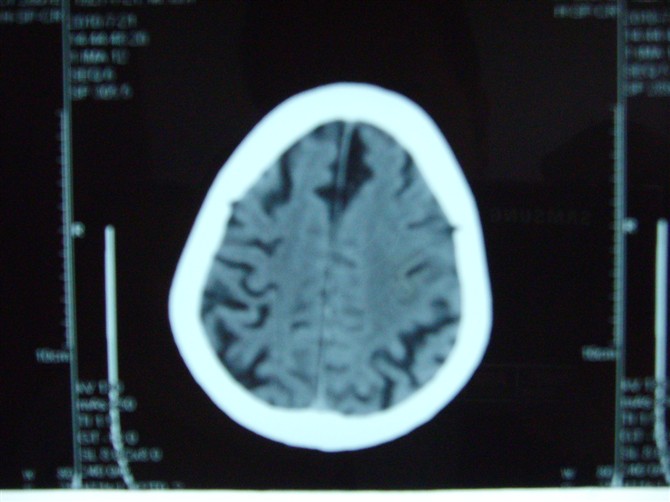

标题: CT27993:男 83岁 头晕伴双下肢无力一天 [打印本页]

标题: CT27993:男 83岁 头晕伴双下肢无力一天

脑萎缩

脑白质疏松症,脑萎缩!

老年脑改变

脑萎缩,脑白质疏松症。

1)双侧小脑半球脑软化灶。2)全脑萎缩。3)脑白质病。